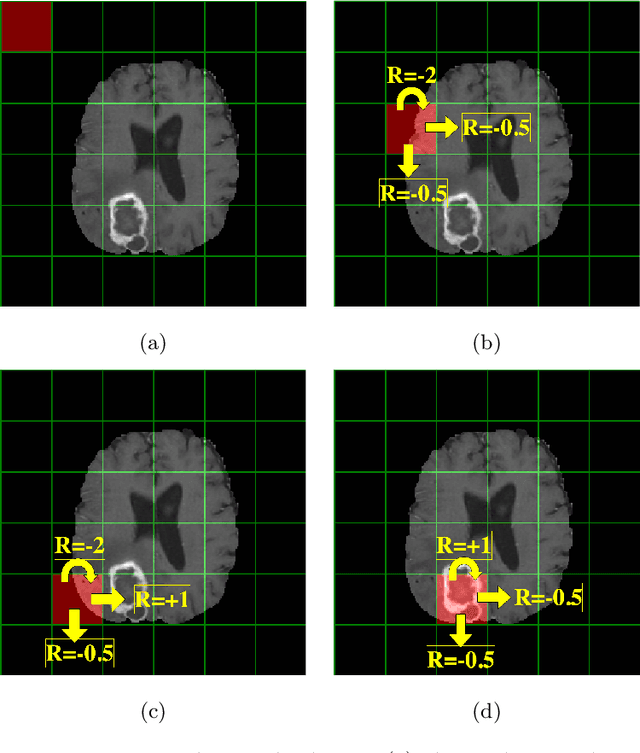

Abstract:Purpose Supervised deep learning in radiology suffers from notorious inherent limitations: 1) It requires large, hand-annotated data sets, 2) It is non-generalizable, and 3) It lacks explainability and intuition. We have recently proposed Reinforcement Learning to address all threes. However, we applied it to images with radiologist eye tracking points, which limits the state-action space. Here we generalize the Deep-Q Learning to a gridworld-based environment, so that only the images and image masks are required. Materials and Methods We trained a Deep Q network on 30 two-dimensional image slices from the BraTS brain tumor database. Each image contained one lesion. We then tested the trained Deep Q network on a separate set of 30 testing set images. For comparison, we also trained and tested a keypoint detection supervised deep learning network for the same set of training / testing images. Results Whereas the supervised approach quickly overfit the training data, and predicably performed poorly on the testing set (11\% accuracy), the Deep-Q learning approach showed progressive improved generalizability to the testing set over training time, reaching 70\% accuracy. Conclusion We have shown a proof-of-principle application of reinforcement learning to radiological images, here using 2D contrast-enhanced MRI brain images with the goal of localizing brain tumors. This represents a generalization of recent work to a gridworld setting, naturally suitable for analyzing medical images.